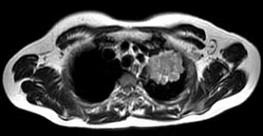

- 单项选择题男,68岁, 声音嘶哑半月,行MRI检查如图, 其最可能的诊断为 ( )

A、右上肺癌

B、左上肺结核球

C、左上肺炎性假瘤

D、左上肺癌

E、左上肺动静脉瘤